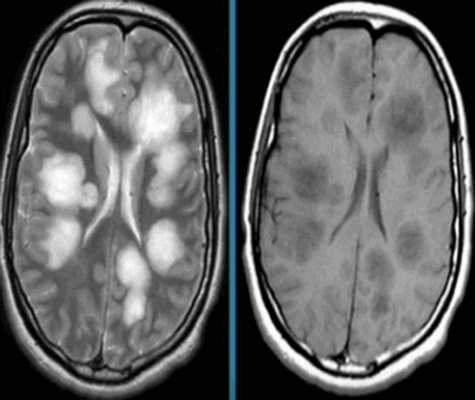

- как уже было сказано ранее, преимущество над КТ в плане отображения мягких тканей, что хорошо видно на картинке выше. МРТ выигрывает при диагностике заболеваний головного и спинного мозга, отдельных органов брюшной полости и органов малого таза.

Перед вами - два снимка, сделанных в одном режиме. Снимок снизу - норма. Какое заболевание, в таком случае, есть на верхнем снимке? Чтобы понять это, нужно сравнить эти изображения. Явно видно отличие - на верхнем снимке в правой части головного мозга есть новообразование. Разница еще заметнее, если сравнить левую и правую части того же снимка.

Отметим его красной окружностью. Визуально оно представляет собой узел, неоднородный по окраске и отличающийся от серого и белого вещества головного мозга. В таких случаях, чтобы точно определить границы опухоли и определить её тип исследование повторяют с контрастом. Введение контрастного препарата в кровь через локтевую вену приводит к накоплению контрастного вещества в тканях опухоли - нормальные здоровые ткани его практически не накапливают. И мы получаем следующую картину, показанную на рисунке справа. Яркая окраска опухоли соответствует накопленному контрасту - теперь можно не только сказать, где опухоль, но и примерно определить, что это доброкачественная опухоль, так как она имеет четкие границы (злокачественные опухоли прорастают окружающие ткани, из-за чего границы будут размытыми и не такими четкими).